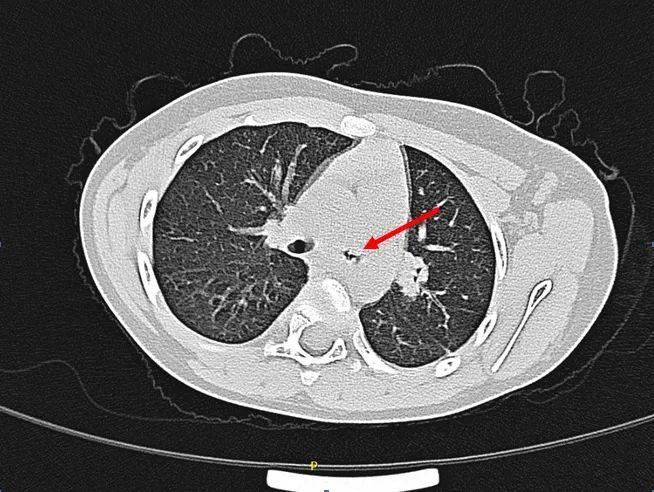

经过检查,在萱萱的左侧支气管近端发现一个高密度影堵塞,局部管腔严重狭窄。经多学科会诊后,扬州大学附属医院儿童支气管镜团队成员徐金梅副主任医师及陶经智主治医师为萱萱实施全麻下支气管镜检查+异物取出术,在手术中医生发现萱萱的左主近端支气管,有大量白色分泌物覆盖,异物深藏其中。由于异物滞留时间长达2个月以上,周围肉芽组织增生明显,支气管几乎被肉芽组织“封堵”,管腔狭窄超过70%,取出难度极大。